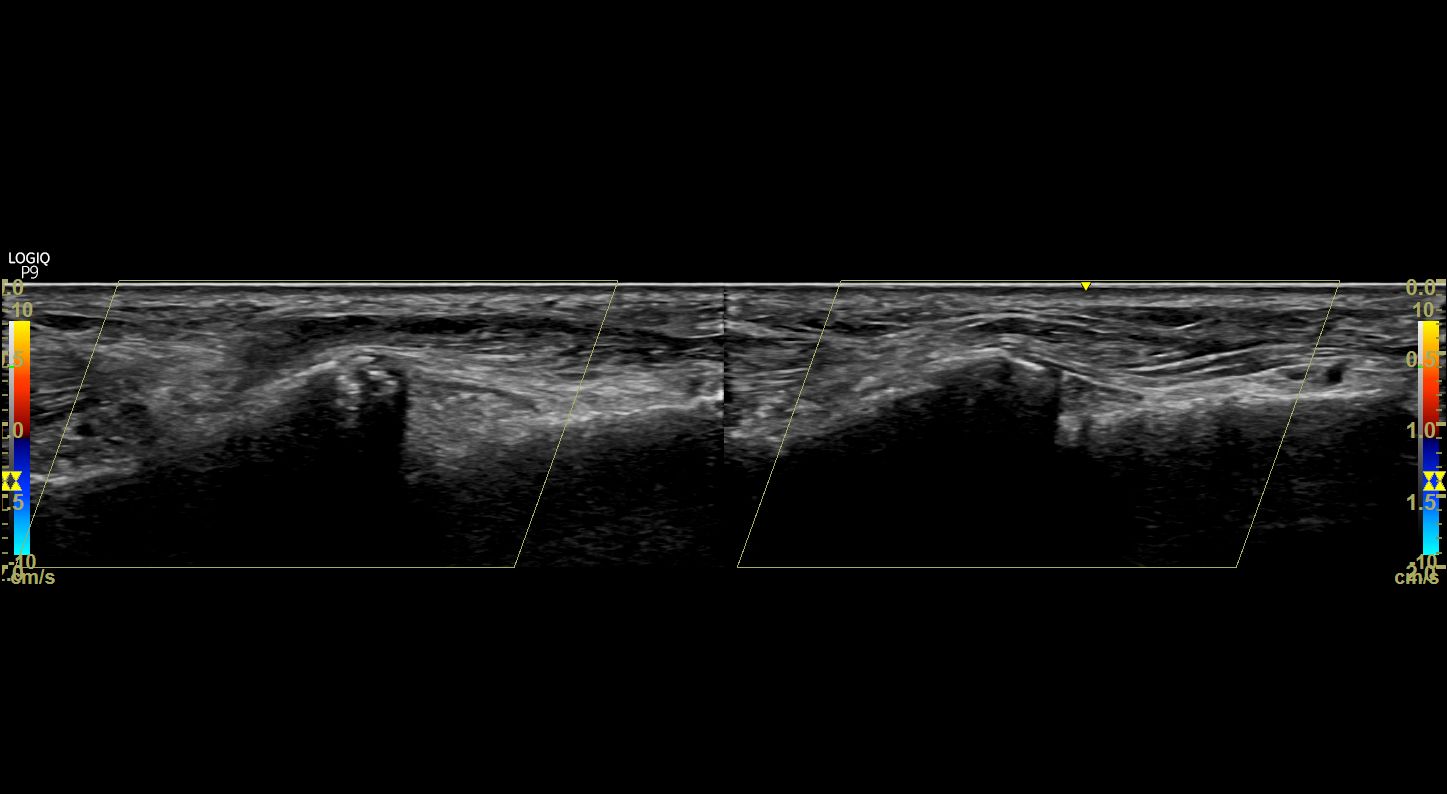

족소양경근에 프로브를 대어

반대쪽과 비교해보았습니다.

왼쪽 영상을 보시면

이분인대가 늘어나면서

종골 전방돌기(anterior process)가

톡 떨어져 나갔네요.

주변 연부 조직도 부어있어

골절이 의심됩니다.